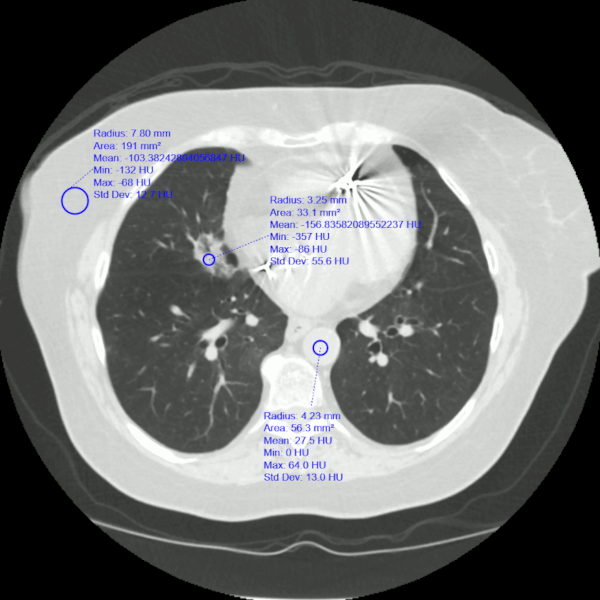

En los casos de aspiración de contenido gástrico, la TC de tórax puede mostrar opacidades en los segmentos posteriores de los lóbulos superiores y los segmentos superiores de los lóbulos inferiores. En los casos avanzados, los hallazgos pueden ser difíciles de distinguir de los del síndrome de dificultad respiratoria aguda (SDRA). La exploración por TC delinea con precisión la ubicación de las opacidades lobulares y segmentarias. La aspiración de grasa (neumonía lipoidea exógena) o material de contraste a veces se puede determinar midiendo la atenuación del tejido en las tomografías computarizadas. El absceso y empiema pulmonar son complicaciones potenciales de la aspiración que se visualizan mejor con una TC que con una radiografía de tórax simple.[73] Véase los apartados Absceso pulmonar y Empiema.

[Figure caption and citation for the preceding image starts]: Neumonía lipoidea. Mujer de 77 años con disfagia y acalasia después de un accidente cerebrovascular que presentó infiltrados pulmonares recurrentes, incluida una lesión persistente del lóbulo medio derecho. La medición de las unidades de Hounsfield (HU) fue de -157, compatible con neumonía lipoidea. Se muestra la grasa subcutánea comparativa y la HU de la aorta (sangre/tejido)De la colección del Dr. Augustine Lee; utilizado con el permiso de la Fundación Mayo para la Educación e Investigación Médica, todos los derechos reservados [Citation ends].